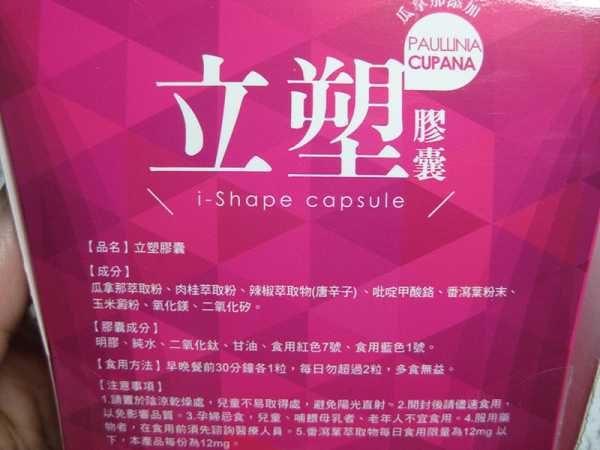

Supercut塑魔纖立塑膠囊的成分有:瓜拿那萃取粉、肉桂萃取粉、辣椒萃取物(唐辛子)、吡啶甲酸鉻、番瀉葉粉末、玉米澱粉、氧化鎂、二氧化矽。

之前上過相關課程,成分表是依照每項成分的多寡來排列順序,排在最前面的就是產品的主要成分!

那我就跟大家分享瓜拿那萃取粉、肉桂萃取粉和辣椒萃取物吧

瓜拿那萃取和辣椒萃取是可以幫助纖體瘦身常見的營養素!

1.「瓜拿那」是原產於亞馬遜流域的一種藤蔓植物,富含酵素可以幫助排便順暢,並且能抑制脂肪分解酵素,此外也有降低食慾的效果喔~~萃取物中含有天然咖啡因,可以提高新陳代謝率以及排出多餘水分!

2.「辣椒萃取物」則是可以幫助體內脂肪燃燒、增加卡路里的消耗,達到防止脂肪積聚的效果

3.「肉桂萃取物」看到肉桂,就想到麥當勞的蘋果派或是手掌麵包,雖然很多人很害怕那味道,但艾哥愛死肉桂了!!!!肉桂在古代被視為是最有價值的東方香料之ㄧ,中世紀時,肉桂的聲望僅次於昂貴的黑胡椒,除了香料和薰香價值, 傳統上肉也被用來治療消化不良、脹氣、關節疼痛、出血和經痛,研究也指出肉桂可以促進新陳代謝喔

食用方式:早晚餐前30分鐘各1粒,每日不超過2粒。(多食無益)

番瀉葉萃取物每日食用限量為12mg以下,

番瀉葉萃取物每日食用限量為12mg以下,